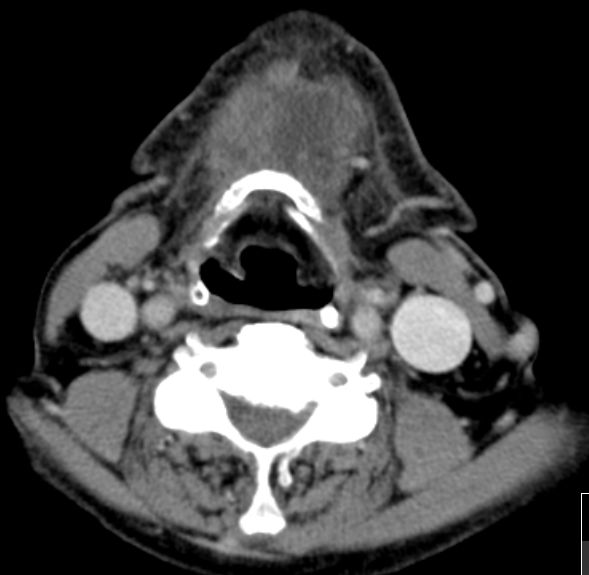

| HNO | 81-jähriger Mann mit einer refraktären Anämie im Rahmen einer Myelodysplasie. Seit einigen Wochen eine rasch wachsende Vorwölbung am Kinn. Intraoperativ infiltrative Gewebeveränderungen, die vom Platysma nicht abzugrenzen sind. Scharfe Absetzung von der Mundbodenmuskulatur. Histologisch zentroblastenänliche Morphologie, CD20 stark positiv, teilweise BCL2-positiv. Keine Expression von S100, Melan A, CK7, EMA, AE1/3, Cyclin D1. CD3 bei nichtläsionalen T-Lymphozyten positiv. |

|||

|

| ||